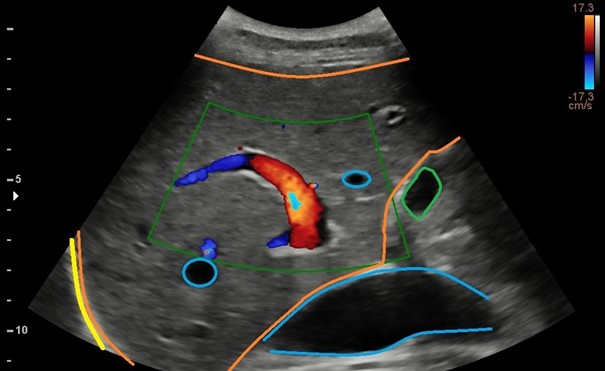

Portale Hypertensie

De vraag naar echografie in het kader van portale hypertensie groeit. Is de richting van de flow in de vena porta alleen bepalend om hierin een uitspraak te doen. Het antwoord is nee!

Tegenwoordig kunnen met de echografie veel meer ten aanzien van de tekenen van portale hypertensie. Ik heb daarvoor een richtlijn ontworpen die gedoceerd wordt op de Post-HBO echografie aan de Inholland Academy.

Met een 2 uur durende bijscholing spijker ik je bij.